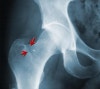

X-ray : 고관절 피로골절(Stress fracture of the hip)

X-ray 검사를 하기는 하지만 확진은 하기 어렵습니다.

전형적인 소견은 저음영선(radiolucent line), 경화(sclerosis), 또는 골막부위의 새로운 뼈 형성(bone formation)이며 이들은 증상 발생 후 2~4주는 되어야 나타납니다.